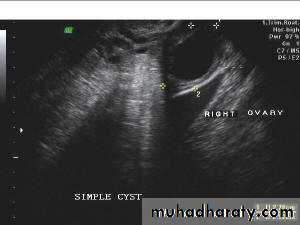

Rt. ovarian simple cyst: